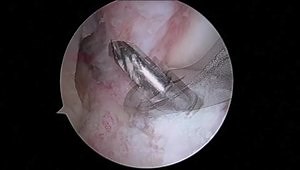

Top suggestions for ACL Reconstruction Technique |

ACL - ACL Reconstruction

and Meniscus Repair